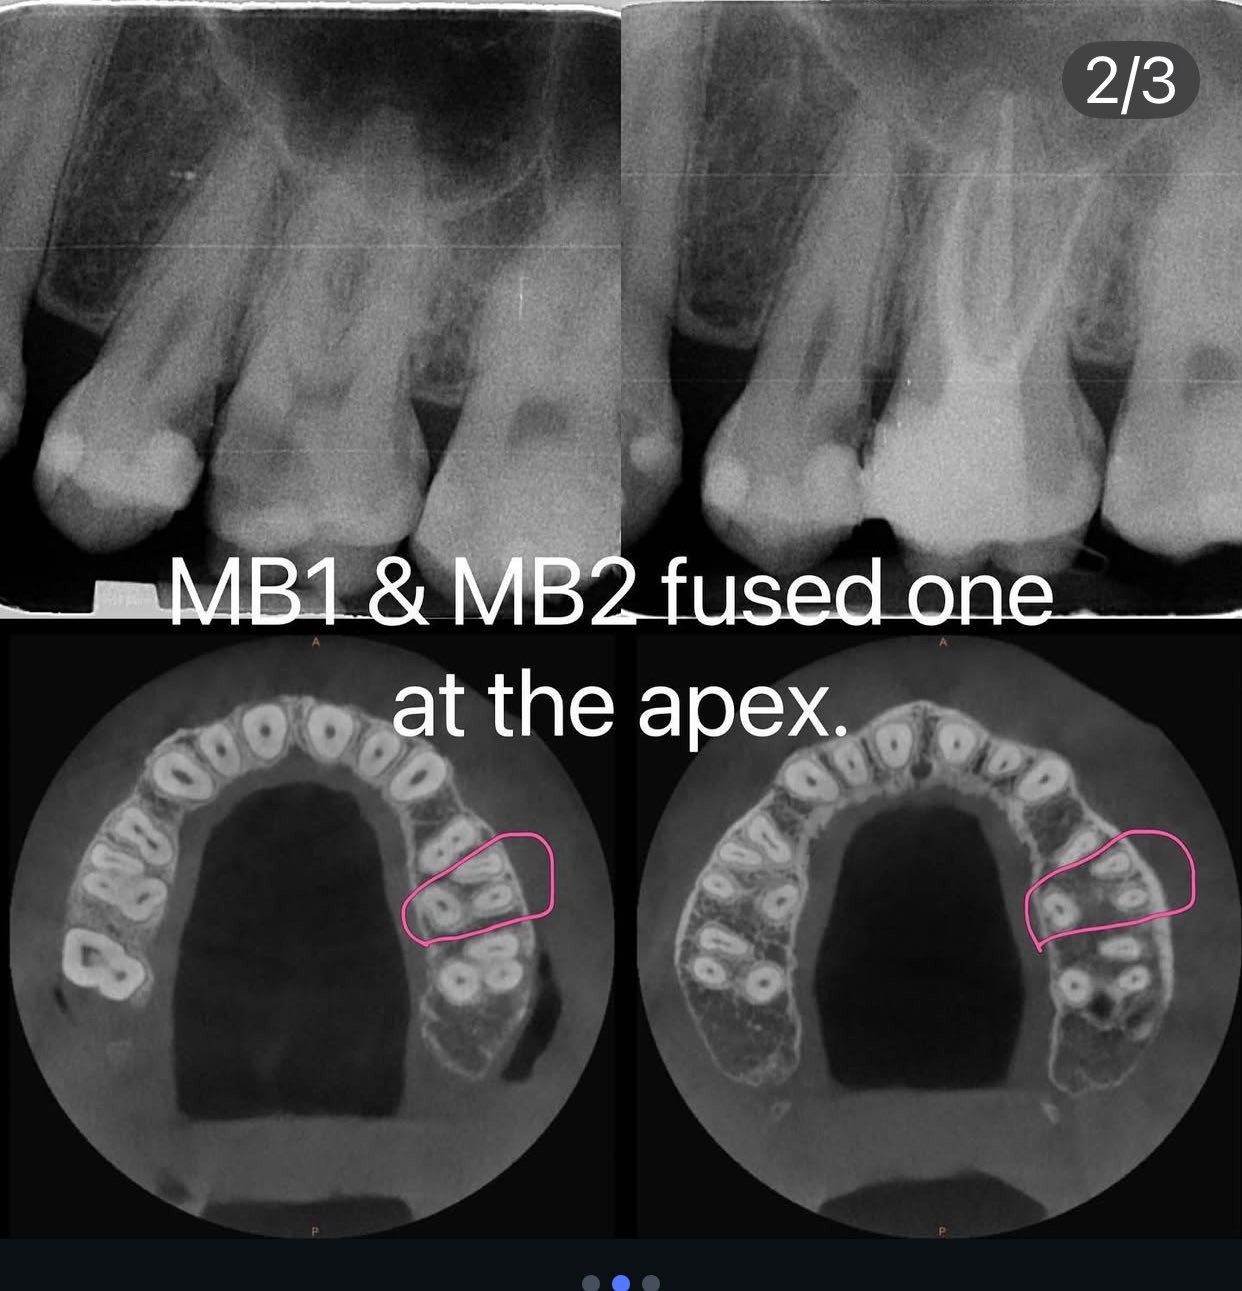

如何找到MB2呢?

常常上面大臼齒的近心頰側牙根會有第二根管,在做根管治療時能夠找到它可以提高根管治療的成功率,以下分享百謙院長找此根管的心得:

1. 從CT的橫切面看,看MB Root是否有兩個洞或狹長橢圓形。

2. 用牙科顯微鏡(放大工具)先把P和DB找到,然後在預設MB1位置(會在MB cusp 下方)的近心顎側找MB2(要看根管的紋路,會有溝紋和洞🕳️的樣態)。

3. 若MB1先找到,那將MB1與P連線,再將DB做一條線垂直此連線,就有機會在對側附近找MB2 。

(圖片部分來自簡院長的IG)